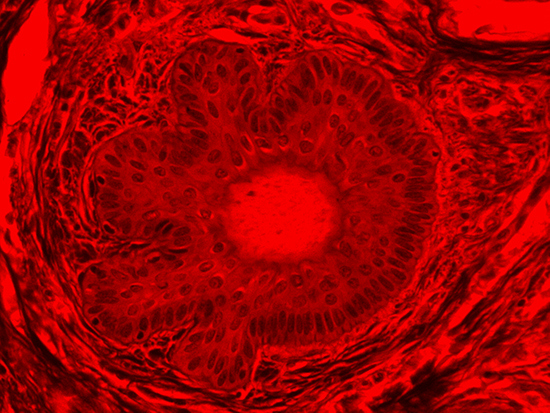

Figure 3: Brightfield Image of Dermal Tissue filtered with Green

Figure 4: Brightfield Image of Dermal Tissue filtered with Red

When comparing Figure 3 with Figure 4, there is once again a significant visual difference. The most obvious feature is the change in color from green to red due to a different hardcoated filter being positioned in the optical path. The less obvious difference is the varying contrast levels caused by the filters at specific regions of the dermal tissue. For example, Figure 3 exhibits a distinct ring at the central region of the cell with additional matter within. In Figure 4, the ring is extremely faint and the internal matter is not visible. With that said, the cell and surrounding dense materials are more evident in Figure 3, whereas the muscle fibers and collagen are more pronounced in Figure 4.